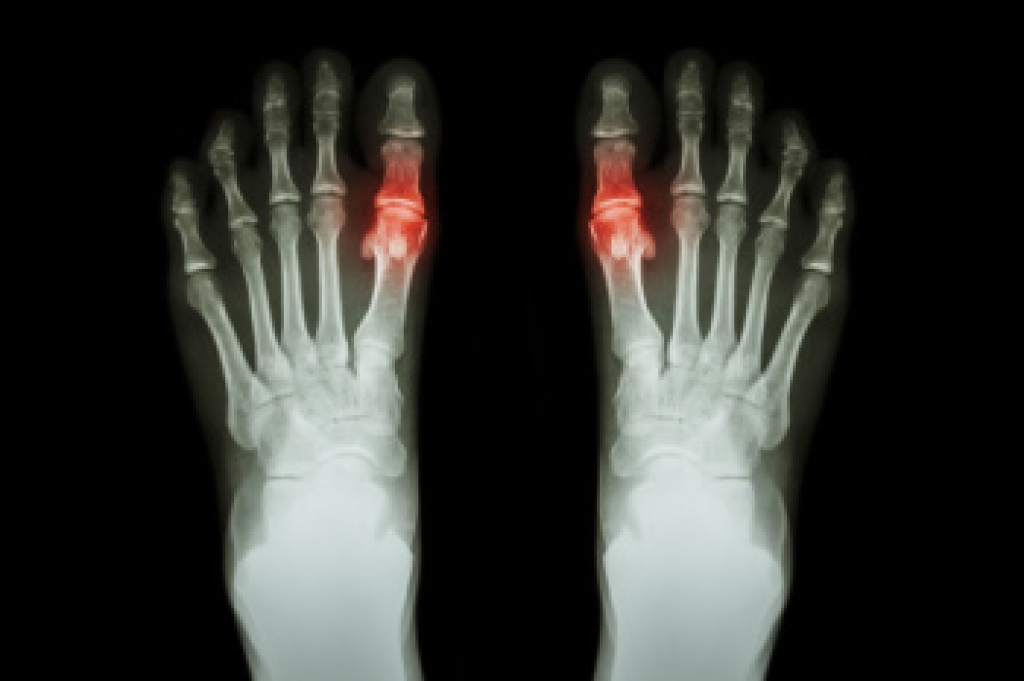

Gout is a form of arthritis that occurs when uric acid builds up in the blood, forming crystals that accumulate in the joints, causing severe pain and swelling. It commonly affects the big toe but can occur in other joints as well. Symptoms of gout include intense, sudden pain, redness, warmth, and swelling in the affected joint. Diagnosing gout typically involves a physical examination, blood tests to check uric acid levels, and sometimes joint fluid analysis to detect uric acid crystals. Living with gout requires managing symptoms and preventing flare-ups. This can be done through dietary changes, such as limiting foods high in purines and taking medications to lower uric acid levels. Regular exercise and maintaining a healthy weight can also help reduce the risk of future attacks. Gout attacks can be excruciating. If this has happened to you, it is strongly suggested that you are under the care of a podiatrist who can help you manage this painful condition.

Gout is a form of arthritis that is characterized by sudden, severe attacks of pain, redness, and tenderness in the joints. The condition usually affects the joint at the base of the big toe. A gout attack can occur at any random time, such as the middle of the night while you are asleep.